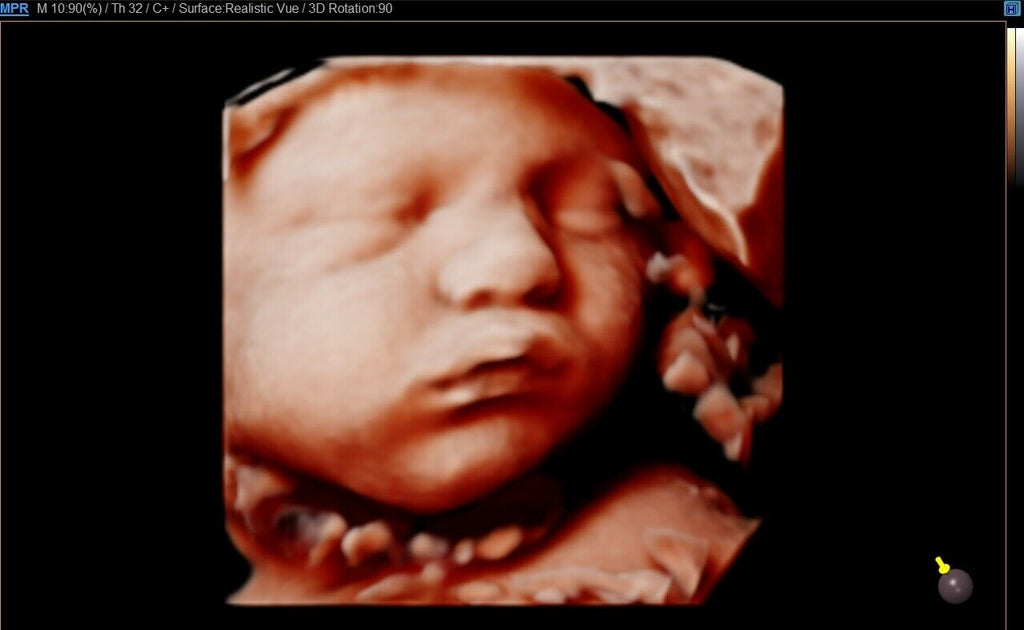

Samsung WS80A Elite Ultrasound and CV1-8 3D Abdominal with Realistic Vue